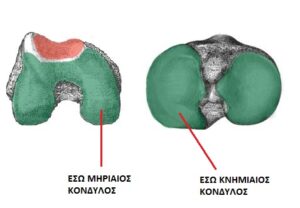

Το γόνατο είναι μια άρθρωση τριών διαμερισμάτων: το έσω διαμέρισμα, που δέχεται και τα περισσότερα φορτία, το έξω και σχετικά πιο ελεύθερο διαμέρισμα, που δέχεται λιγότερα φορτία και το διαμέρισμα της επιγονατιδομηριαίας άρθρωσης. Το τελευταίο, επίσης δέχεται σημαντικά φορτία, λόγω της συμμετοχής του στον εκτατικό μηχανισμό. Όπως είδαμε, η οστεοαρθρίτιδα ή εκφυλιστική ή πρωτοπαθής αρθρίτιδα ή απλά αρθρίτιδα, είναι μια συχνή κατάσταση. Για λόγους μηχανικούς, η αρθρίτιδα του γόνατος σε ένα ποσοστό πάνω από 90% ξεκινά από την έσω πλευρά της άρθρωσης. Η αρθρίτιδα λοιπόν, αρχικά προσβάλει το χόνδρο που καλύπτει τις αρθρικές επιφάνειες του έσω κονδύλου του μηρού και του έσω κονδύλου της κνήμης. (εικόνα 1 ) .Η φθορά προκαλεί λέπτυνση, τράχυνση των επιφανειών και αυξημένη τριβή. Συχνά συνυπάρχει εκφυλιστική ρήξη του έσω μηνίσκου.

Στην προχωρημένη αρθρίτιδα, το γόνατο, στο σύνολό του, δε μπορεί να διασωθεί. Η ολική αρθροπλαστική του γόνατος είναι η μόνη λύση. Στην αρθρίτιδα, ωστόσο, που περιορίζεται στην έσω πλευρά, (εικόνα 2 ) μπορούμε, με τις σωστές ενδείξεις, που θα συζητήσουμε αναλυτικά, να προσφέρουμε μια λύση λειτουργικά εξαιρετική και την ίδια στιγμή πολύ πιο ατραυματική, τη μονοδιαμερισματική αρθροπλαστική του γόνατος.